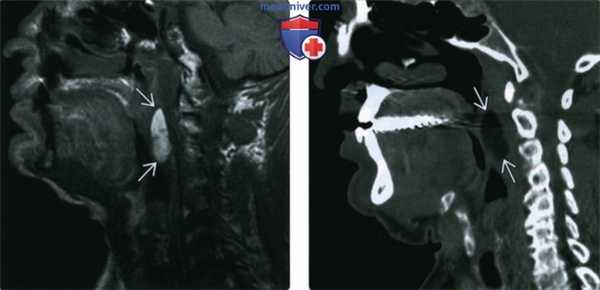

(Слева) МРТ Т1ВИ без гадолиния, сагиттальная проекция. Дольчатое образование в заглоточном пространстве с четкими контурами.

(Справа) КТ с КУ, сагиттальная реконструкция, этот же пациент спустя пять лет. Размеры или контуры образования не изменились. Образование имеет однородную плотность на уровне плотности жировой ткани, контрасте толще опухоли не накапливается. Неизменность образования в течение лет является признаком доброкачественной липомы.